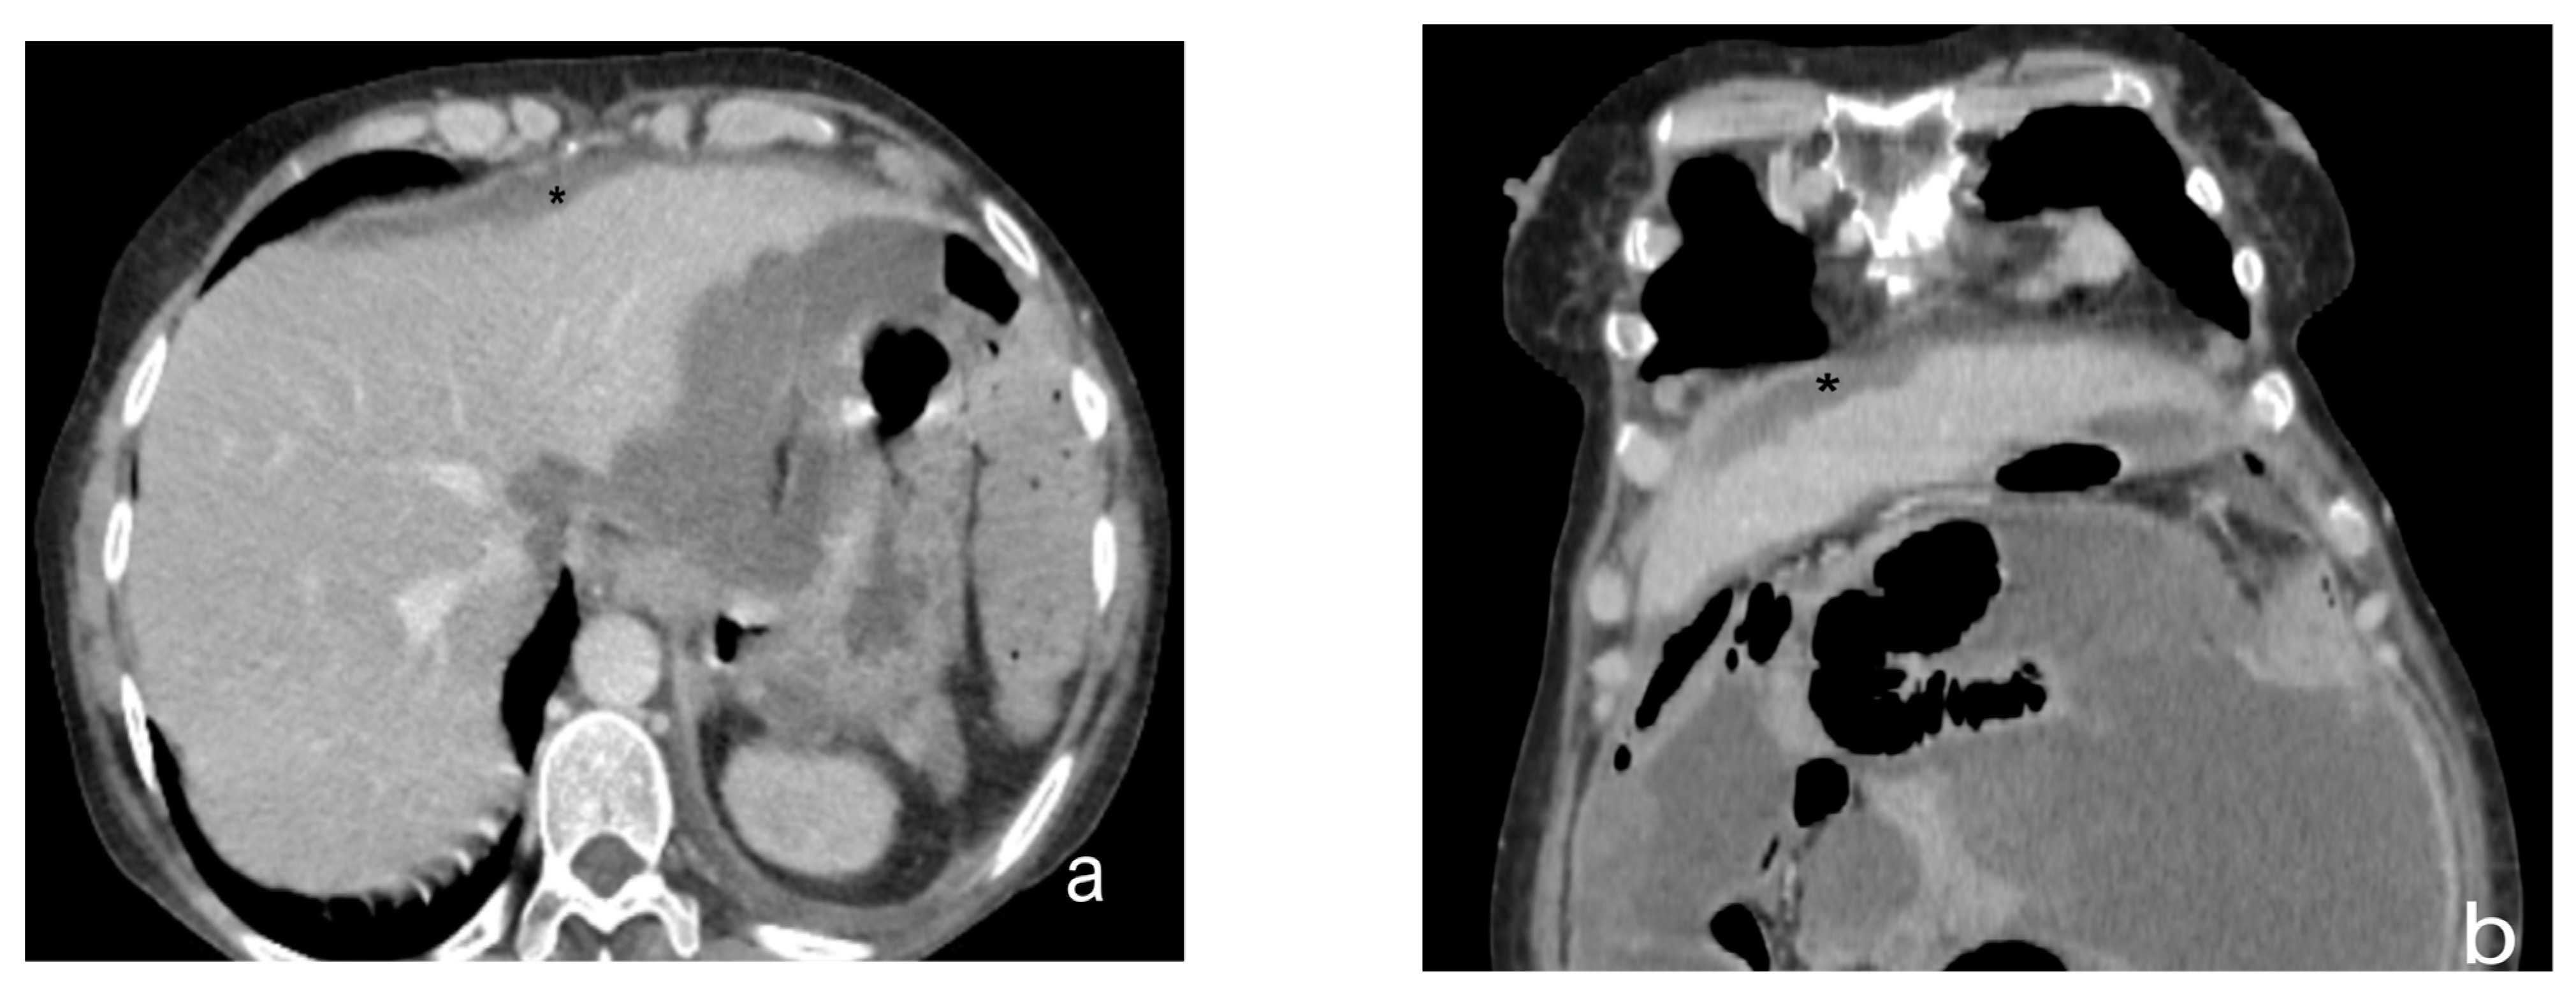

- Mesenteral root involvementDisease in the small bowel and intestinal mesentery constitutes a sentinel and limiting criterion in decision making in CRS. Therefore, the evaluation of small-bowel loops and their mesentery should be a key component in the preoperative imaging evaluation of a patient with PC [24]. The diffuse involvement of the mesentery root is, in fact, a criterion for unresectability. Thin mesenteral tumor sheets are invisible on CT and PET scans [111]. In a study of 30 cases by Dromain et al. [87], CT detected implants in the small bowel in 26% of cases, whereas the true incidence of this disease location at the time of surgery was 83%.Furthermore, MRI has been reported to be superior to CT in the evaluation of the intestinal tract and mesenteric involvement in light of its high capacity in soft-tissue studies [112].Diffuse small-bowel involvement (mesentery and/or intestinal serosa) remains difficult to represent, however, and when present, the radiologist should estimate the extent of involvement as less than or greater than 50%. The radiologist should also describe the number and location of any stenosis of segments of the small intestine, as well as invasion of the colon or gastric system, to produce a complete analysis of the entire digestive tract [69].Indeed, Jacquet et al. [43] found that when preoperative CT showed a tumor causing intestinal obstruction, surgical cytoreduction was suboptimal in 88% of cases. If the tumor obstructing the jejunum or superior ileum was greater than 5 cm in diameter, no subject had a complete CRS.In fact, the two radiologic findings that Sugarbaker et al. [113] reported as most strongly associated with poor outcomes in CRS are the presence of tumor nodules greater than 5 cm on small-bowel surfaces and segmental small-bowel obstruction.Preoperative imaging can aid in patient selection by avoiding surgery for patients whose tumors are excessively large for adequate surgical cytoreduction; in particular MRI using gadolinium and DWI sequences routinely describe tumor-cell sheets involving the serosa of the small intestine and mesentery, which are typically not seen on CT or PET [55] (Figure 14 and Figure 15).